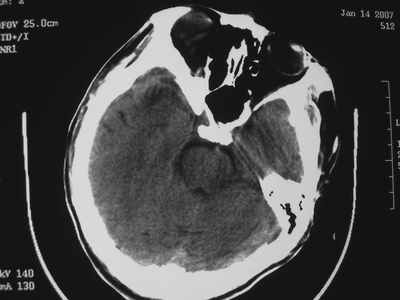

以下是引用卜一在2007-1-19 15:29:00的发言:[br]治疗前:1月14日右侧额叶皮质下低密度影,而治疗后:1月18日右侧阴影消失,新近出现左侧额叶侧脑室前角旁大片状低密度影,边缘模糊。支持—双侧额叶后部缺血性脑梗塞。